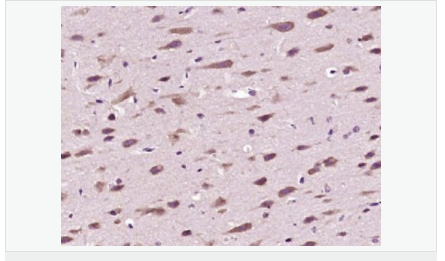

交叉反應:Human,Mouse,Rat(predicted:Pig,Cow,Horse,Rabbit) 推薦應用:IHC-P,IHC-F,IF,ELISA

| 產品應用 | ELISA=1:5000-10000 IHC-P=1:100-500 IHC-F=1:100-500 IF=1:100-500 (石蠟切片需做抗原修復) not yet tested in other applications. optimal dilutions/concentrations should be determined by the end user. |